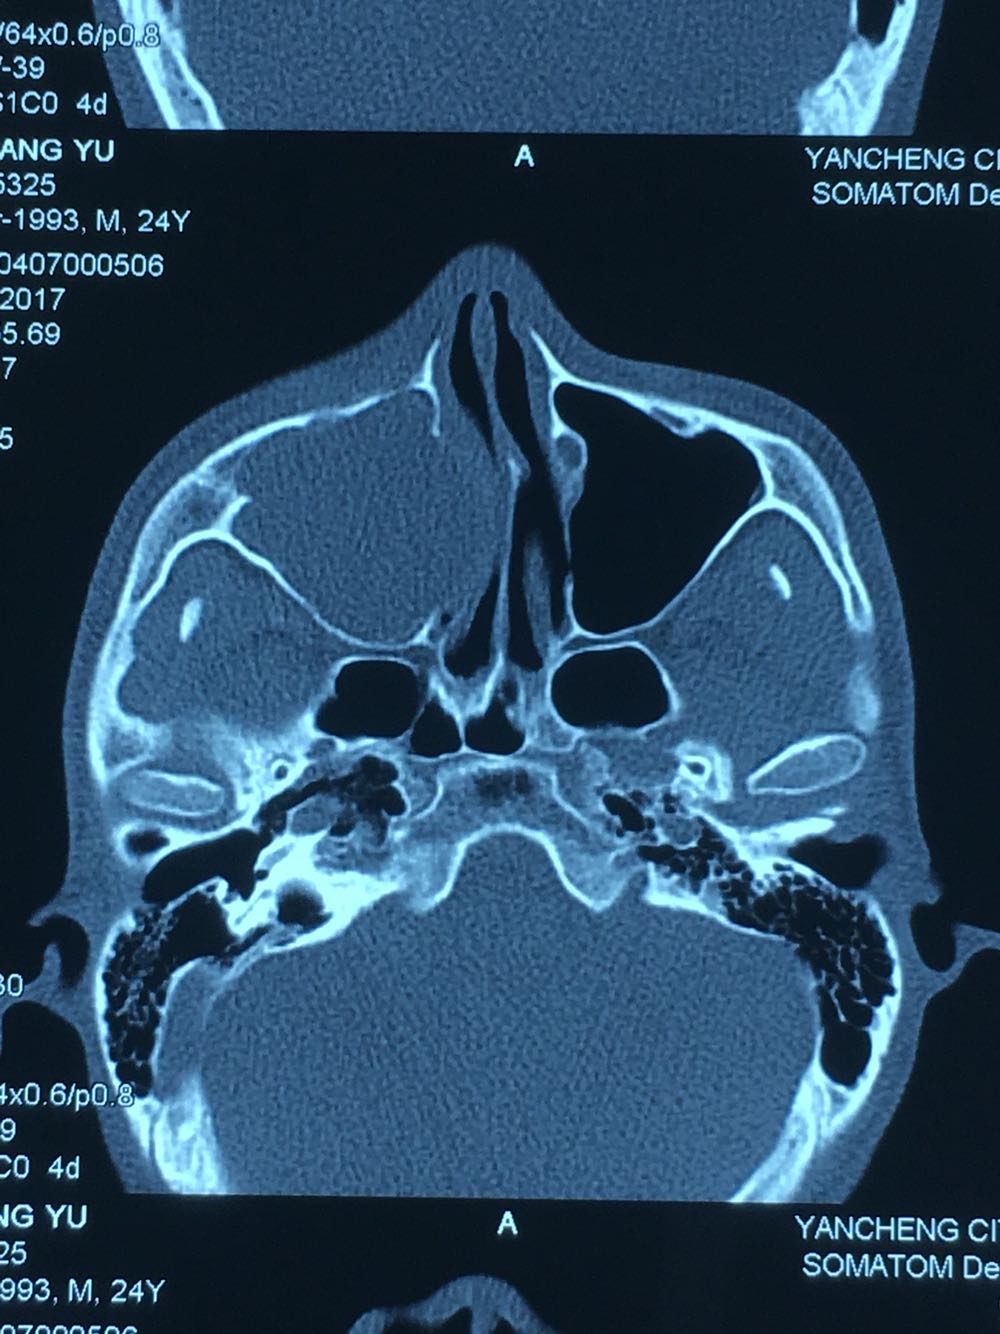

查体:面部明显不对称,右上颌膨隆明显,右鼻翼抬高,眶下区无麻木感,眼球运动自如,13牙齿缺如,16-22牙齿唇侧前庭肿胀,中央扪及波动感,边缘乒乓感,相关牙齿1度松动。 辅查:穿刺,抽得淡黄色液体,全景及CT,上颌骨囊肿,右侧上颌骨骨质大部分破坏

诊断:右上颌骨囊肿,13埋伏阻生。 治疗:开窗减压,拔除13阻生牙齿